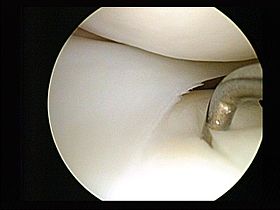

Arthroscopic view showing two of the wrist bones.

Arthroscopy of the wrist is used to investigate and treat symptoms of repetitive strain injury, fractures of the wrist and torn or damaged ligaments. It can also be used to ascertain joint damage caused by wrist osteoarthritis.